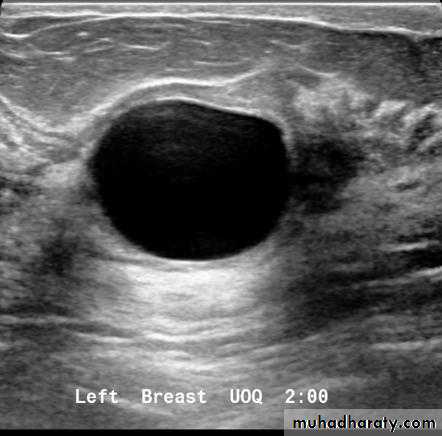

Cysts can be simple fluid-filled sacs (known as simple cysts) or can be partially solid (known as complex cystic and solid masses). Simple cysts are benign (not cancer) and don’t need to be biopsied. If a mass is not a simple cyst, it is of more concern and might need to be biopsied to be sure it isn’t cancer

Cyst